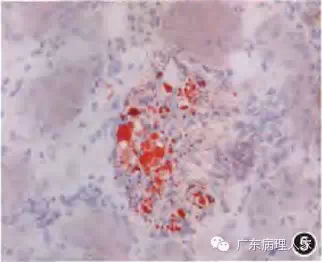

1.肾活检的病理诊断必须密切联系临床,虽然任何病理检查均须与临床表现联系来思考,但对肾活检病理诊断而言,这一点更为重要。因为同一种病理表现可能对应着截然不同的临床肾脏病,由于临床治疗方法不同,一旦误诊,将造成不良后果,如一种以系膜细胞和内皮细胞弥漫增生为特点的肾小球病变,有急性链球菌感染后肾小球肾炎、病毒感染后肾小球肾炎、活动性弥漫增生性狼疮性肾炎(图1)、IgA肾病(图2)、过敏性紫癜性肾炎等多种可能,决定性因素是临床表现和化验指征。另者,同一临床肾脏疾病可有不同的病理表现,仍以临床确诊为系统性红斑狼疮而导致的狼疮性肾炎为例,可分为轻微病变型、轻度系膜增生型、局灶增生型、弥漫球性增生型、弥漫节段增生型、膜增生型、新月体型、膜型、增生硬化和硬化型多种病理类型。所以,从事肾活检病理诊断的病理医师,一定要具备必要的临床肾脏疾病知识。

图1 毛细血管内增生性狼疮性肾炎,肾小球内皮细胞和系膜细胞弥漫增生 PASM染色 高倍放大